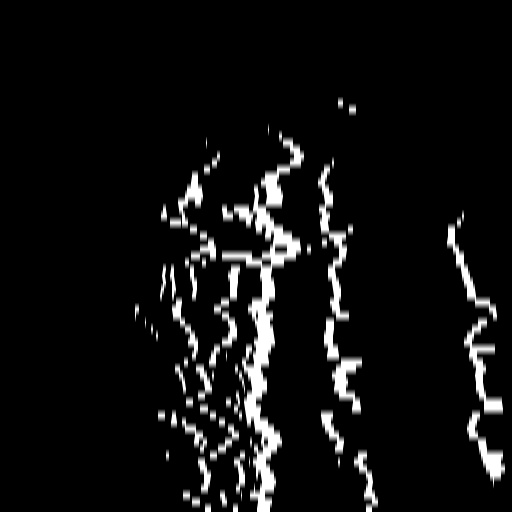

Parallel vessel motion loss .

We conduct an experiment to assess the effect of the parallel vessel motion loss by removing it from the training pipeline. As shown in Table 2, the segmentation performance decreases the Dice score by 0.0368. Without this loss to enforce parallelism between blood and vessels, the segmentation results are negatively affected. In addition, the comparison between without and with is shown in Figure 9 (c). The zoom-in patch shows that the image with has clearer segmented vascular regions.